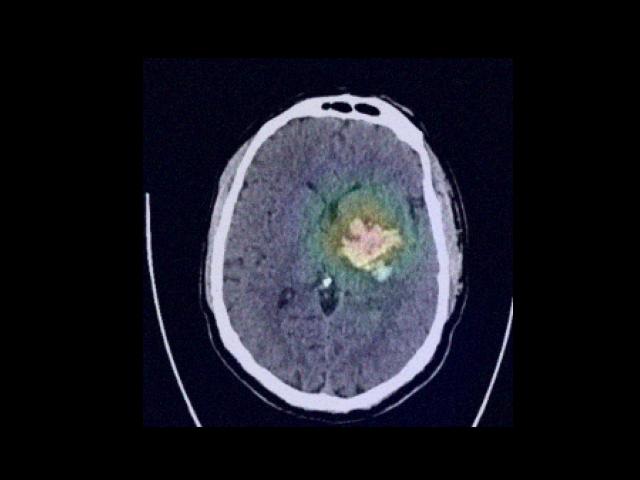

Sample Gallery